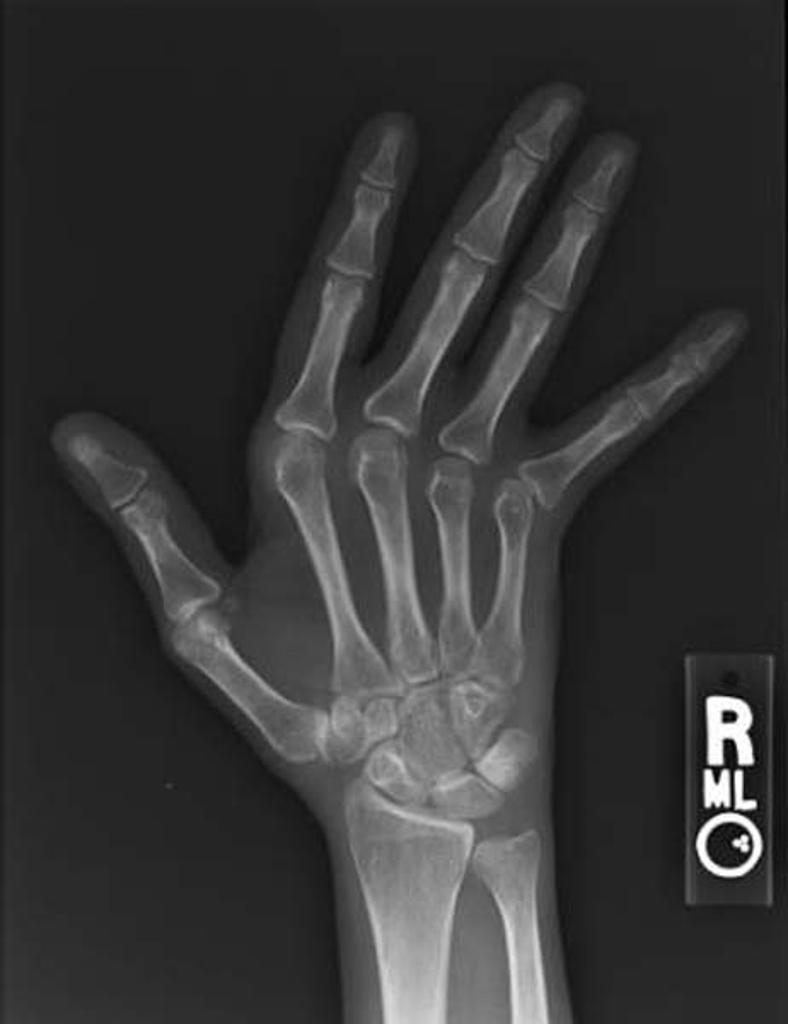

dystrophic soft tissue calcs plus acroosteolysis

scleroderma

Acroosteolysis and dystrophic soft tissue calcs

fingertips affected first with atrophy of the distal soft tissues

scleroderma ** neuropathy polyvinyl chloride exposure thermal injury hyperparathyroidism Hajdu-Cheney